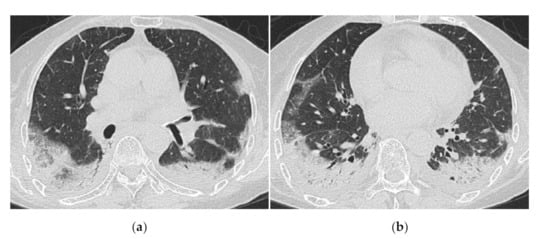

2.1. Subacute to Chronic Type

HRCT Findings of Patients with Anti-ARS Ab

| Subacute course of disease > chronic | Acute or subacute onset, often with a rapid progressive course |

| Predominantly in the lower lobes of both lungs | Diffuse, or diffuse with a predominance of the lower lung zone |

| Peribronchovascular bundle distribution | Peribronchovascular distribution in the lower lobes, with parallel extension to the pleura |

| Reticular shadows and consolidation are common | GGO and consolidation |

| Reduced volume of the lower lobes | Basal volume loss |

| Traction bronchiectasis |